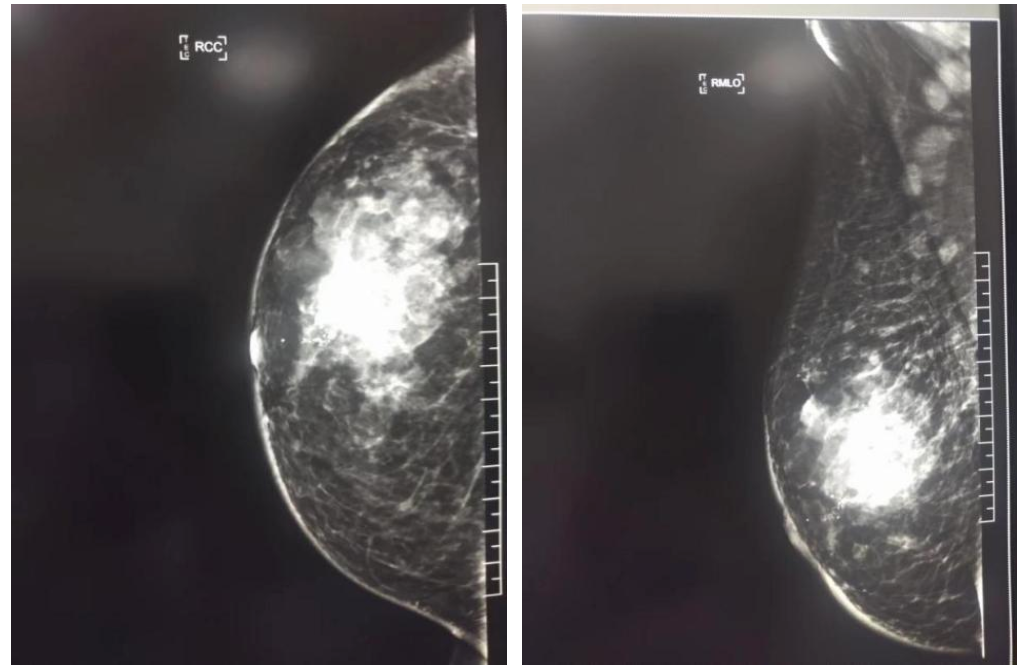

2021年12月8日,双侧乳腺钼靶影像表现:右乳外上可见高密度肿物影,大小约6.7×6.2cm,形态不规则,密度不均匀,边缘可见分叶,另可见粗大钙化,皮肤增厚,乳头未见异常;左乳末见异常。右腋下可见增大淋巴结,最大者短径约1.7cm,左侧腋下可见小淋巴结。印象:右乳恶性肿瘤伴腋下淋巴结转移,BI-RADS分级为5级。

图1.右乳及右腋下钼靶